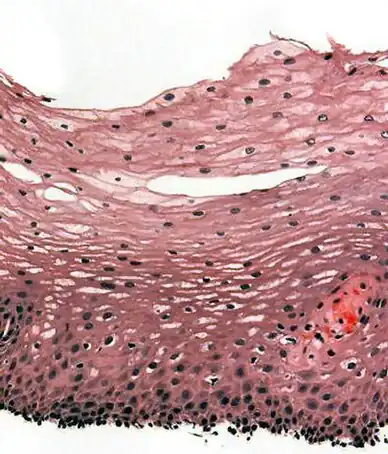

Section of the human skin showing the stratified squamous epithelial surface, referred to as the epidermis. The layer of keratin here is named the stratum corneum. | |

A stratified squamous epithelium consists of squamous (flattened) epithelial cells arranged in layers upon a basal membrane. Only one layer is in contact with the basement membrane; the other layers adhere to one another to maintain structural integrity. Although this epithelium is referred to as squamous, many cells within the layers may not be flattened; this is due to the convention of naming epithelia according to the cell type at the surface. In the deeper layers, the cells may be columnar or cuboidal.[1] There are no intercellular spaces. This type of epithelium is well suited to areas in the body subject to constant abrasion, as the thickest layers can be sequentially sloughed off and replaced before the basement membrane is exposed. It forms the outermost layer of the skin and the inner lining of the mouth, esophagus and vagina.[2]

In the epidermis of skin in mammals, reptiles, and birds, the layer of keratin in the outer layer of the stratified squamous epithelial surface is named the stratum corneum. Stratum corneum is made up of squamous cells which are keratinized and dead. These are shed periodically.